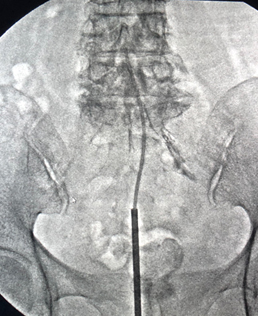

硬膜外腔癒着剥離術

尾骨に近い仙骨裂孔という骨の亀裂から脊柱管の内部にカテーテルを挿入する手術です。局所麻酔で施行することができるため、患者様への負担が非常に小さいのが特徴です。当院では腰部脊柱管狭窄症をはじめとする腰椎疾患の多くに効果をあげています。

ごく稀に骨の形状などで本手術の適応とならない方もいますので、担当医とご相談ください。